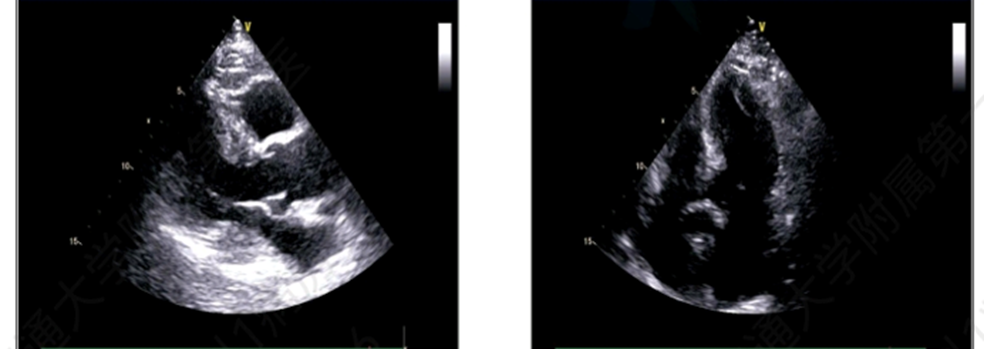

•  超声心动图示,升主动脉增宽、左室舒缓功能减低;

图3 超声心动图